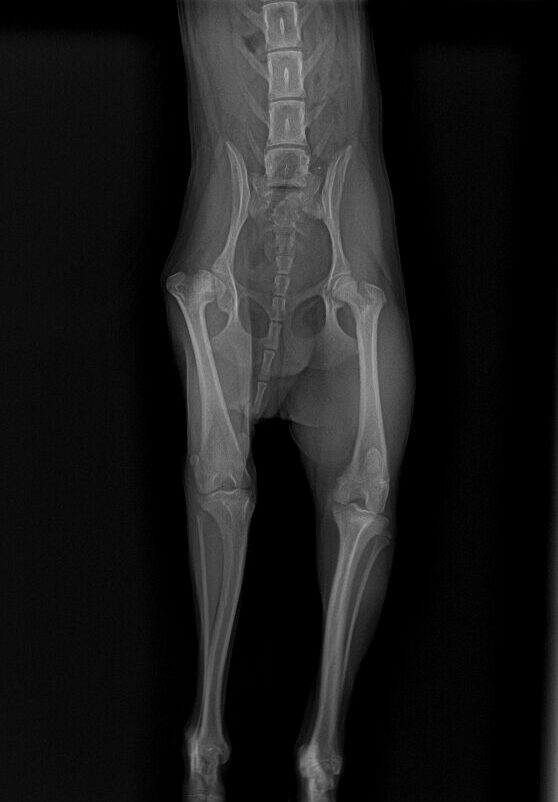

症例は 8ヶ月のヨークシャーテリアで1ヶ月前から片足を着いていないとの主訴で来院しました。

レントゲンを取ると右の股関節(左側)が変形していることが分かります。大腿骨頭が壊死している影響で痛みが出ている可能性が高い状態でした。左右の筋肉量を比較すると右足(左側)の筋肉が萎縮しており、長期間右後肢を使っていなかったことが分かります。